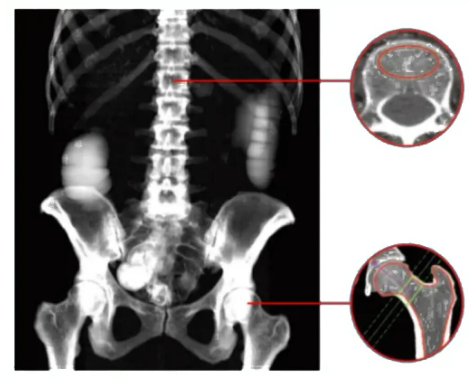

除了精準診斷骨質疏松癥,光子時代的QCT在臨床應用上還有更廣闊的拓展空間。結合iCare QCT的髖部三維分析技術,能夠為髖部疾病診斷與風險評估提供了更全面的視角。相較于傳統(tǒng)二維影像只能呈現(xiàn)局部平面信息,該技術通過構建髖部三維模型,可清晰展現(xiàn)股骨頭、髖臼等結構的空間形態(tài)、位置關系及細微病變,不僅能更準確地診斷髖關節(jié)炎、股骨頭壞死等疾病,還能對髖部骨折風險進行量化評估,為臨床制定個性化治療方案與預防策略提供重要依據(jù)。光子時代的QCT檢測可以為骨科術前評價提供更詳細準確的骨骼信息,幫助醫(yī)生制定更完善的手術方案;在肝臟脂肪含量和腹部脂肪測量方面,也能提供更精準的數(shù)據(jù),為代謝性疾病的診斷和治療提供有力參考。此外,對于一些藥物治療效果的監(jiān)測,通過精確的骨密度測量變化,醫(yī)生可以及時調(diào)整治療方案,提高治療效果。

image.png